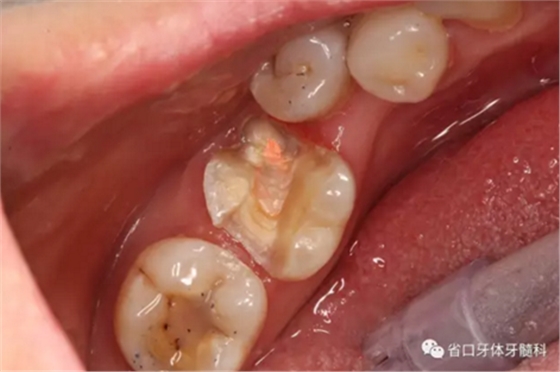

處置:46/清理髓腔,自酸蝕粘接,流動樹脂覆蓋根管口,牙體預備

圖3 牙體預備后,近中頰側牙體缺損平齊齦緣;近頰根管口流動樹脂覆蓋牙膠不足,下次改進